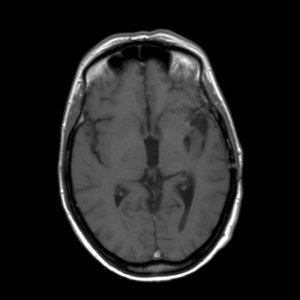

Een astrocytoom graad III groeit onbehandeld snel door in het omliggende hersenweefsel; de ziektegeschiedenis is daarom meestal relatief kort. De meeste patiënten zijn tussen de 30 en 50 jaar oud, iets vaker mannen dan vrouwen. Een MRI toont meestal een grillige, slecht begrensde tumor die met contrast kan aankleuren. De diagnose moet gesteld worden door onderzoek van het weefsel.

'Hoe is het mogelijk, dit kan niet, dit is bizar, zoiets heb ik nog nooit gezien maar het is waar'. Dit waren de woorden van de neuro-oncoloog. Mijn vriendin Ineke en ik bogen ons naar haar computer waar het onverklaarbare resultaat stond. Op de MRI-scan was te zien dat de kwaadaardige tumor zich had teruggetrokken. De tumor had een donkere holte met een grillige tumorrand achtergelaten. De neuro-oncoloog benadrukte nog eens dat het echt heel bijzonder was en dat zij en de radioloog voor een raadsel stonden. Ik vroeg haar wat dit betekende voor de prognose van mijn levensverwachting. Ze zei dat er nog één of misschien zelfs twee jaar zou bijkomen. Meer durfde ze er ook niet over te zeggen.

De MRI scans van 2006 en 2007 zijn niet correct geïnterpreteerd. Wat toen als tumorgroei werd gezien blijkt nu een reactie van de bestraling te zijn. De chemokuur was overbodig omdat de tumor niet groeide. Wat je nu ziet is de tumor die enigzins gegroeid lijkt, maar dat is niet zeker. Als het zeker is moet je overwegen om opnieuw bestraald te worden. Meer patienten zijn ook met de verkeerde boodschap (dat de tumor groeit) naar huis gegaan,ook in andere ziekenhuizen.

Je moet je realiseren dat een MRI een plaatje is waarop een proces zichtbaar wordt oa door aankleuring met contrast. Met een MRI kun je dus vervolgen of een “proces” groter of kleiner wordt. Maar een MRI geeft geen inzicht in de aard van het proces, je weet niet welke cellen toegenomen zijn.

De MRI na de bestraling liet zien dat het ‘proces”in jouw hersenen gegroeid was. Omdat men wist met een kwaadaardige tumor te maken te hebben, is daaruit de op dat moment voor de hand liggende conclusie getrokken dat de radiotherapie helaas niet geholpen had. Na de aanname dat de radiotherapie niet geholpen leek te hebben heeft men het voorstel voor chemotherapie gedaan. Naar mijn mening op goede gronden. Helaas blijkt vaker dat als de tijd verstrijkt je voor verrassingen kan komen te staan zoals ook in jouw geval. Toen na een hele tijd een MRI werd herhaald bleek ‘het proces’in de hersenen eerder kleiner te zijn geworden dan de groei die men eigenlijk had verwacht. Op dat moment heeft men de conclusie moeten trekken dat de toename van het proces na de bestraling dus een gevolg moet zijn geweest van de bestraling een soort oedeem (zwelling) tgv de straling. Deze conclusie is echter alleen te maken door het beloop in de tijd en deze conclusie was niet te maken in een eerder stadium.

Dit betekent ook dat het vanaf nu wel zinnig is om met enige regelmaat de MRI te vervolgen. Mocht er ooit weer op de MRI een toename van het proces gezien worden dan is namelijk opnieuw radiotherapie een goede behandelingsmogelijkheid. (chemo ligt wat minder voor de hand omdat je dat slecht hebt verdragen).Je moet alleen pas overwegen te gaan behandelen als op de laatste MRI duidelijk een groei te zien is van het proces, weet jij of de laatste MRI een verschil aangaf met de vorige? Als je het goed vindt kan ik in het UMCG ook de gemaakte MRI’s van jou bekijken als het jou niet helemaal duidelijk is geworden.

Op de scan was sprake van enige aankleuring, maar de neuro-oncoloog is er van overtuigd dat het geen tumorgroei is maar nog een oedeem van de bestraling. Volgens haar duwt de tumor andere cellen aan de kant en een oedeem doet dat niet. Bovendien is de aankleuring ook a-typisch wat betekent dat hij niet als ronding begint en juist dát hoort bij een glioom.